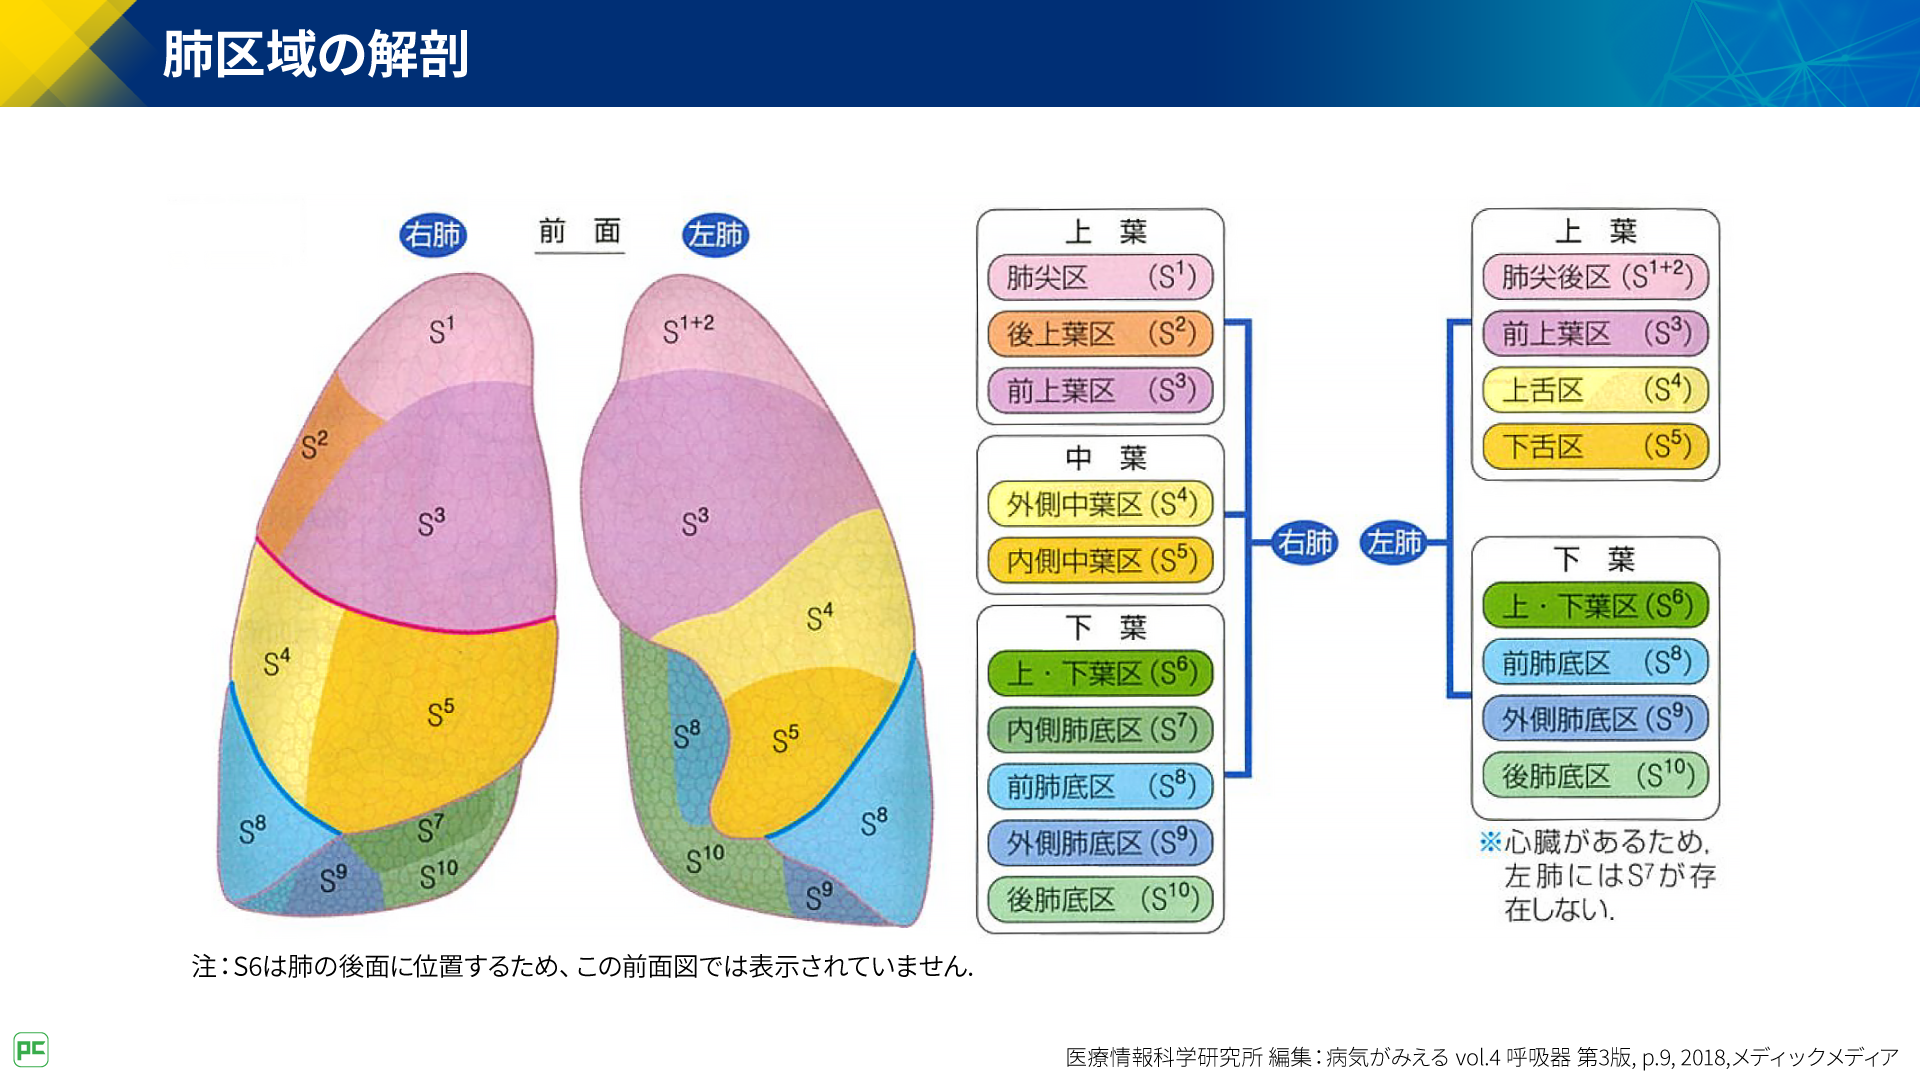

インポート・海外人気ブランド 気管支の枝読みで考える Amazon.co.jp: 胸部画像診断入門 Books Japanese 功(清仁会宇多津病院放射線科画像診断センター長): 佐藤 : ─ 電子版付 ─ 肺既存構造と区域解剖学から学ぶ読影の基礎 ── 医学一般

インポート・海外人気ブランド 気管支の枝読みで考える Amazon.co.jp: 胸部画像診断入門 Books Japanese 功(清仁会宇多津病院放射線科画像診断センター長): 佐藤 : ─ 電子版付 ─ 肺既存構造と区域解剖学から学ぶ読影の基礎 ── 医学一般

Amazon.co.jp: 気管支の枝読みで考える 胸部画像診断入門 ── 肺既存構造と区域解剖学から学ぶ読影の基礎 ─ 電子版付 ─ : 佐藤 功(清仁会宇多津病院放射線科画像診断センター長): Japanese Books,

Amazon.co.jp: 気管支の枝読みで考える 胸部画像診断入門 ── 肺既存構造と区域解剖学から学ぶ読影の基礎 ─ 電子版付 ─ : 佐藤 功(清仁会宇多津病院放射線科画像診断センター長): Japanese Books, 呼吸器疾患診療における胸部HRCT画像読影のポイント(静止画)|べーリンガープラス,

呼吸器疾患診療における胸部HRCT画像読影のポイント(静止画)|べーリンガープラス, X線診断の基礎知識|胸部写真の読み方|太田東こども&おとな診療所|こどもとおとなの病気について、気軽に相談できる診療所です。,

X線診断の基礎知識|胸部写真の読み方|太田東こども&おとな診療所|こどもとおとなの病気について、気軽に相談できる診療所です。, レジデントノート増刊:読影力がグッと上がる!胸部X線写真・CTの読み方、考え方〜疾患別に読影の基本と各科での経過観察のポイント、撮影のタイミングがイチからわかる! - 羊土社,

レジデントノート増刊:読影力がグッと上がる!胸部X線写真・CTの読み方、考え方〜疾患別に読影の基本と各科での経過観察のポイント、撮影のタイミングがイチからわかる! - 羊土社, Amazon.co.jp: 気管支の枝読みで考える 胸部画像診断入門 ── 肺既存構造と区域解剖学から学ぶ読影の基礎 ─ 電子版付 ─ : 佐藤 功(清仁会宇多津病院放射線科画像診断センター長): Japanese Books